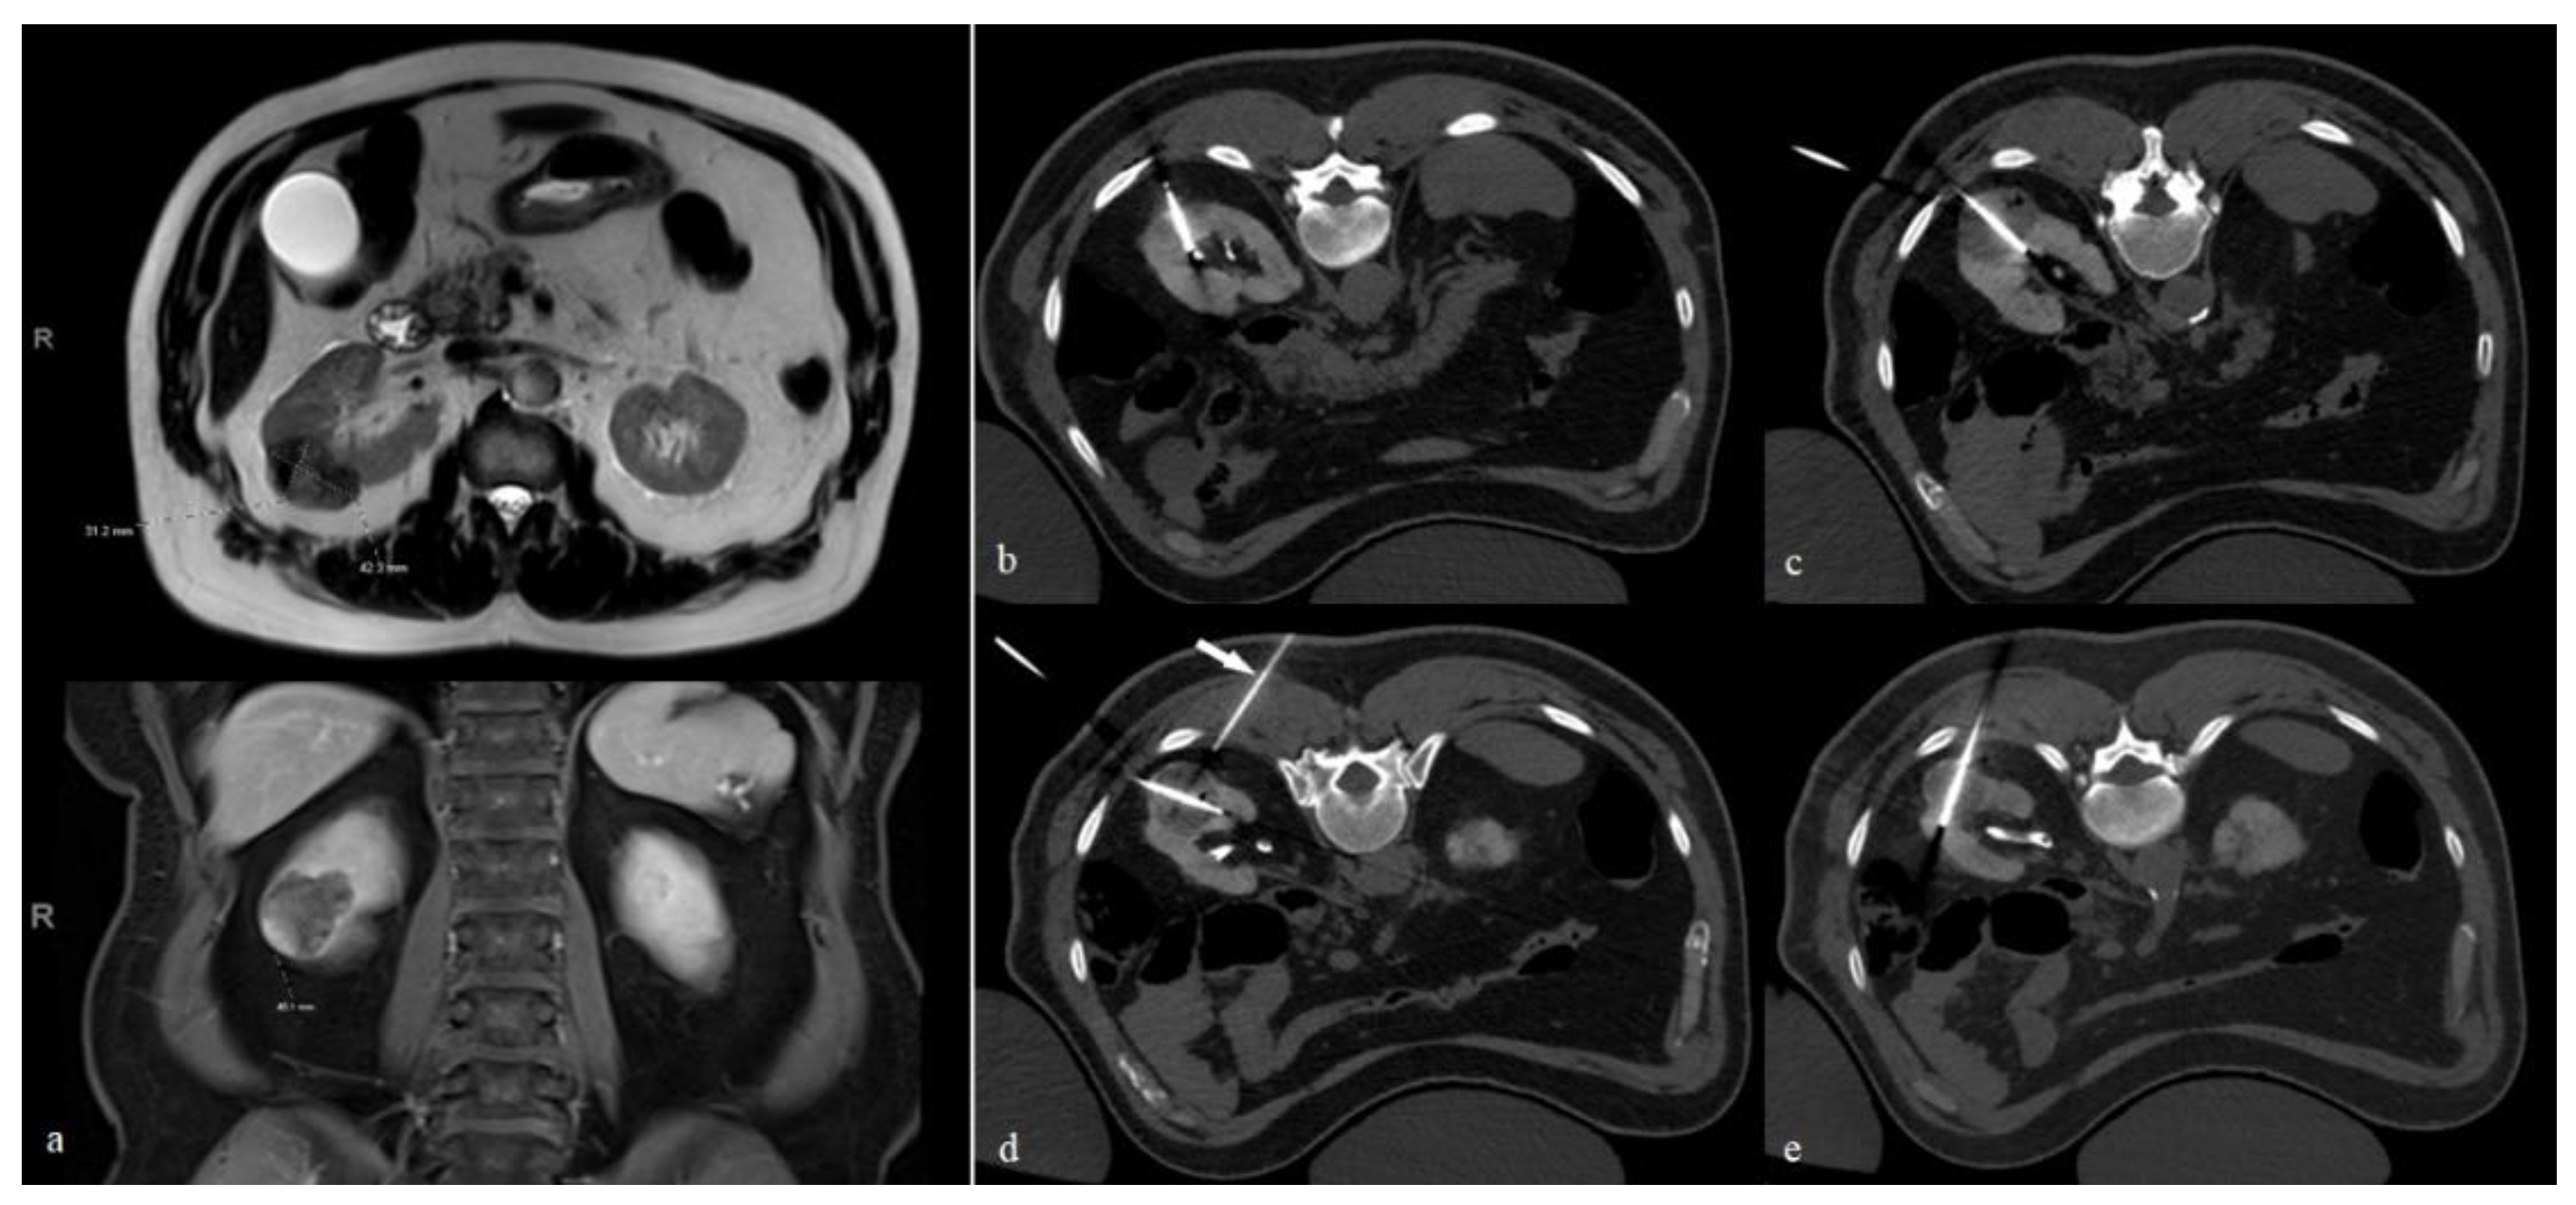

Figure 1. Cryoablation of a right renal RCC. (a) MRI scan shows a right renal partly exophytic mass, measuring 4.2 × 3.1 × 4.5 cm along the axial and craniocaudal dimensions, respectively. (be) Four cryoablation probes are carefully aligned along the longitudinal axis of the mass from cranial to caudal. In our experience, the orientation of the probe shown in figure (e) is critical as it allows the ice ball to ablate the most central part of the mass, which is a common site for recurrence. The arrow in (d) points to a 21 G needle used for CO2 dissection, as shown in Figure 2.

Generally, better outcomes can be achieved by placing cryoprobes parallel to the longitudinal axis of the lesion. This is particularly important when using cryoprobes with larger ablation zones, such as the IceFORCE ® 2.1 CX (Galil Medical Inc., MN, USA), which usually produces an ice ball that is greater in length than width. However, the non-uniform shape of these tumors can make probe placement along the longitudinal axis technically challenging. In our experience, the most challenging portions to ablate are the central and medial aspects of the tumor. These are also frequent sites of recurrence [9]. In this case, we recommend placing at least one probe along the longitudinal access of the lesion in the craniocaudal center and toward the medial aspect of the tumor (Figure 1).

Multiple cryoprobes, with 3–5 probes on average, are usually needed to treat large RCCs. To allow for the appropriate coalescence of the separate ice balls, we recommend a spacing of 1.5–2 cm between the probes. In our practice, we typically start by targeting the cranial and then the caudal ends of the tumor. We then place at least one probe along the longitudinal axis at the central/medial aspect of the lesion. We then fill in the gaps between the three initial probes using 1–2 additional probes. An effort is made to avoid traversing the back musculature, if possible. Care is also taken to minimize crossing the normal renal parenchyma as much as possible, although exceptions can be made to ensure appropriate coverage of the target lesion. Careful planning is essential to avoid non-target freezing of intercostal nerves, the genitofemoral nerve, and adjacent bowel loops.